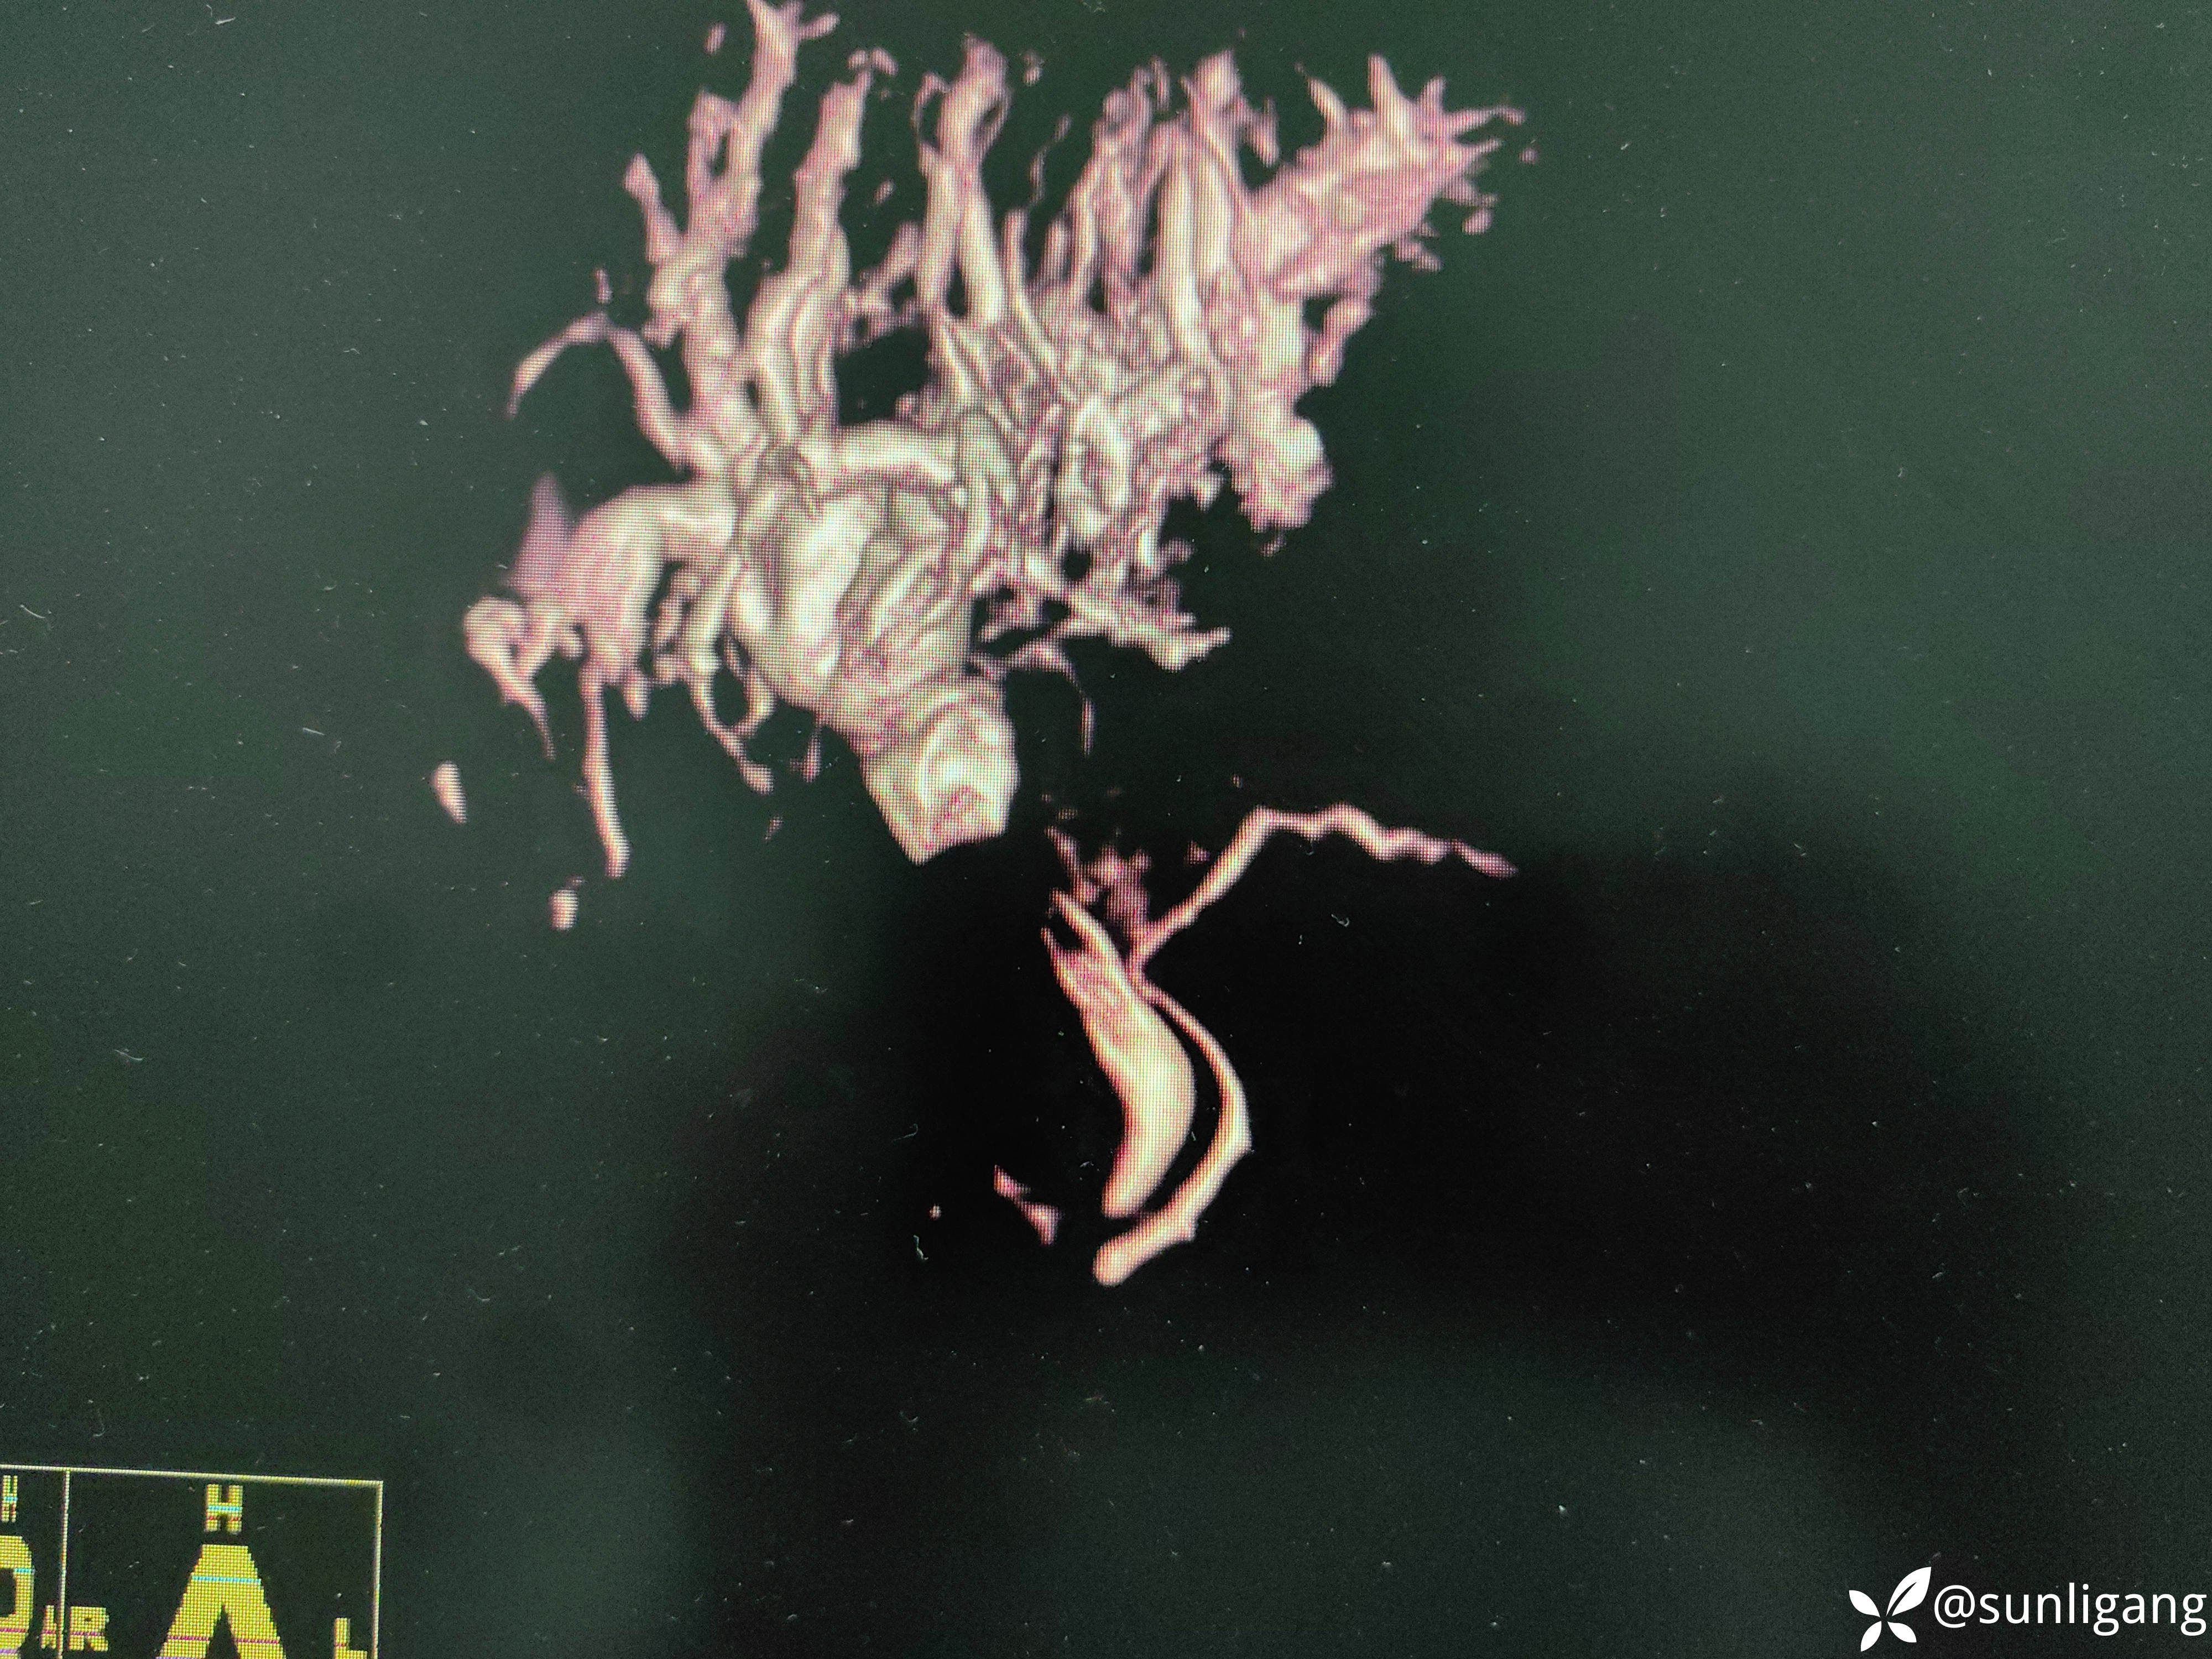

三维重建: